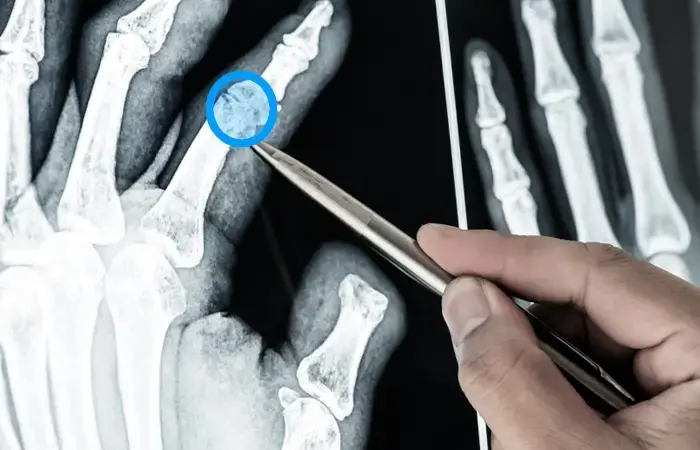

Annotation for Point of Interest in X-Rays

Annotating medical datasets to create high-quality training data to be used in AI-powered clinical models to monitor X-ray images with enhanced diagnostic accuracy and reduced disease detection time.